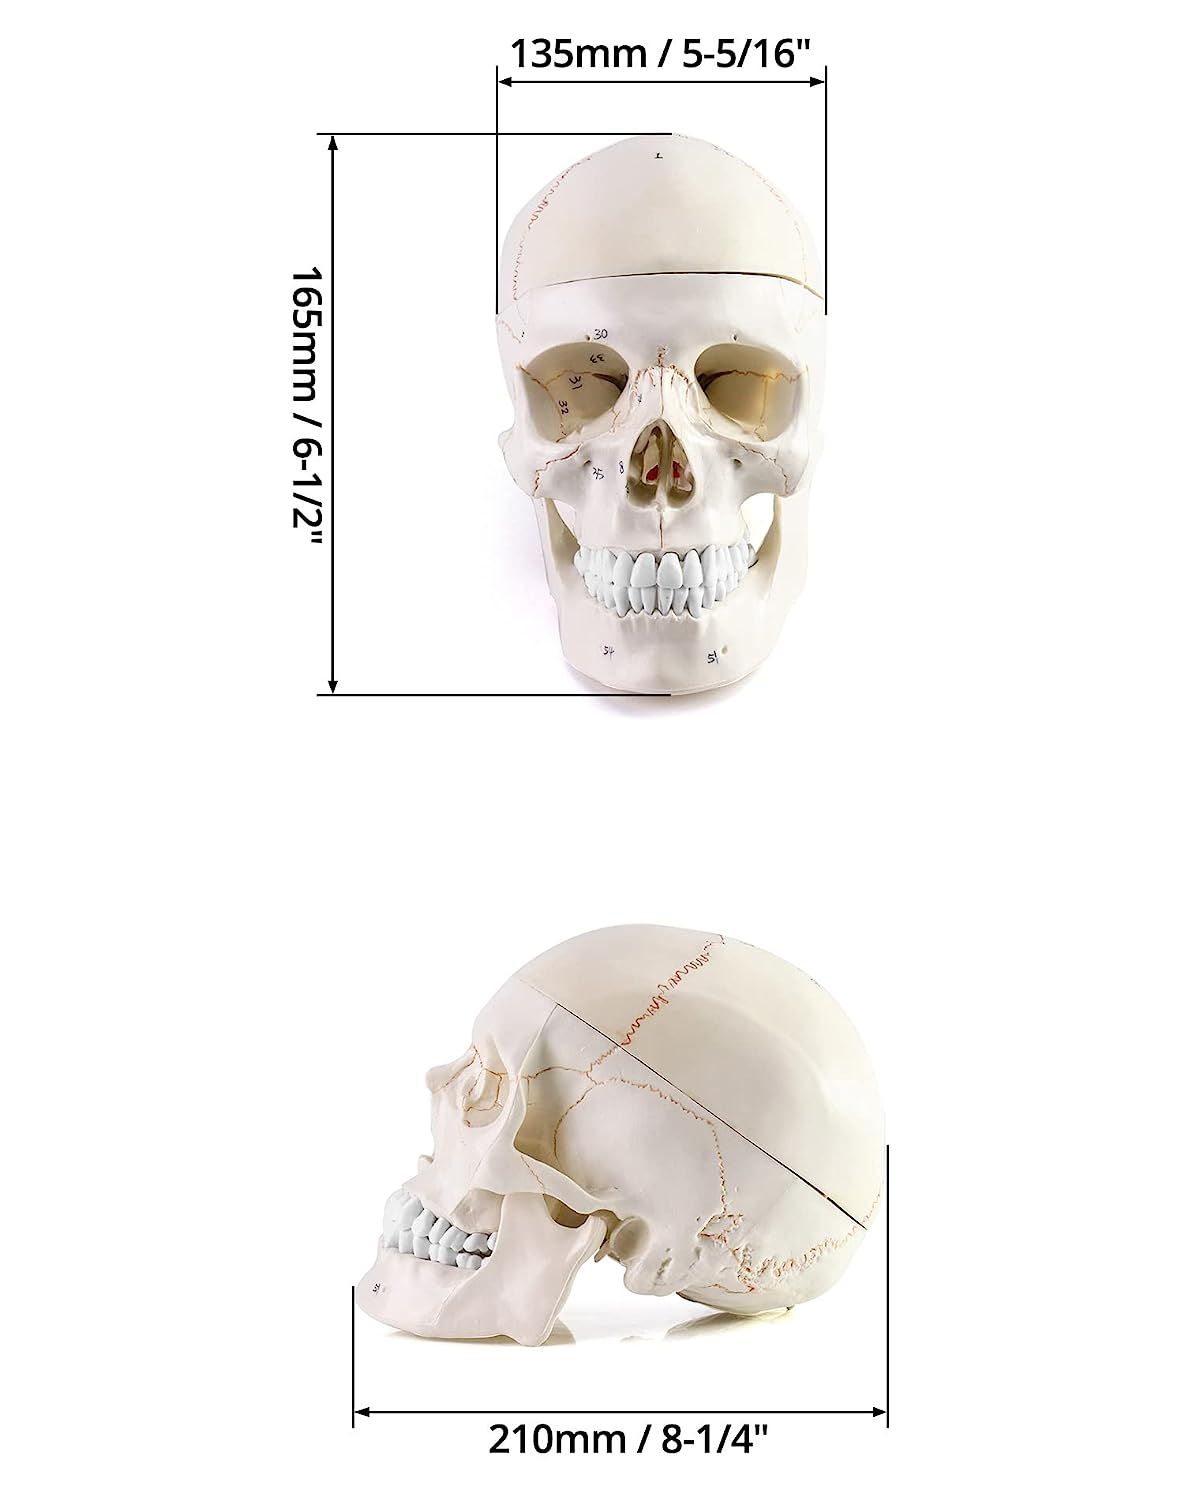

Package Dimensions : 8.7 x 8.66 x 6.61 inches; 3.35 Pounds

Life Size: Life size human skull and brain model allow you clearly see all the main anatomical structures of the human skull and brain, perfect for patient education or anatomical study.

11 Part: The skull model consists of 3 part. The brain model consists of 8 components: sagittal section of brain, cerebral hemisphere, cerebellum and brainstem.

Numeric Marker: The brain model features a labeled diagram for 32 numeric marker. The skull model includes a labeled diagram for 55 numeric marker.

Durable Material: Made of premium PVC material. Light-weight, high strength, anti-corrosion, long term service.

The skull model consists of 3 part.

Sturdy Construction

The connection is fixed with steel nails, so that the entire skull structure is stable and not loose.

Numeric Marker

The brain model features a labeled diagram for 32 numeric marker. The skull model includes a labeled diagram for 55 numeric marker.

11 Part

The skull model consists of 3 part. The brain model consists of 8 components: sagittal section of brain, cerebral hemisphere, cerebellum and brainstem.

Life Size

Life size human skull and brain model allow you clearly see all the main anatomical structures of the human skull and brain, perfect for patient education or anatomical study.

| Product model | Human Skull with brain 8 parts model |

| Type | Anatomical skeleton model |

| Size | 21x16x21cm |

| Weight | 1.8kg |

The model is composed of three parts of skull model and eight parts of brain model, which are made manually according to the 1:1 ratio of human body. Among them, the skull is made manually with strong and broken food grade PVC, which shows the cerebellar sulcus, hole, process, bone suture, etc. with high accuracy. It can be divided into skull cap, skull base and mandible